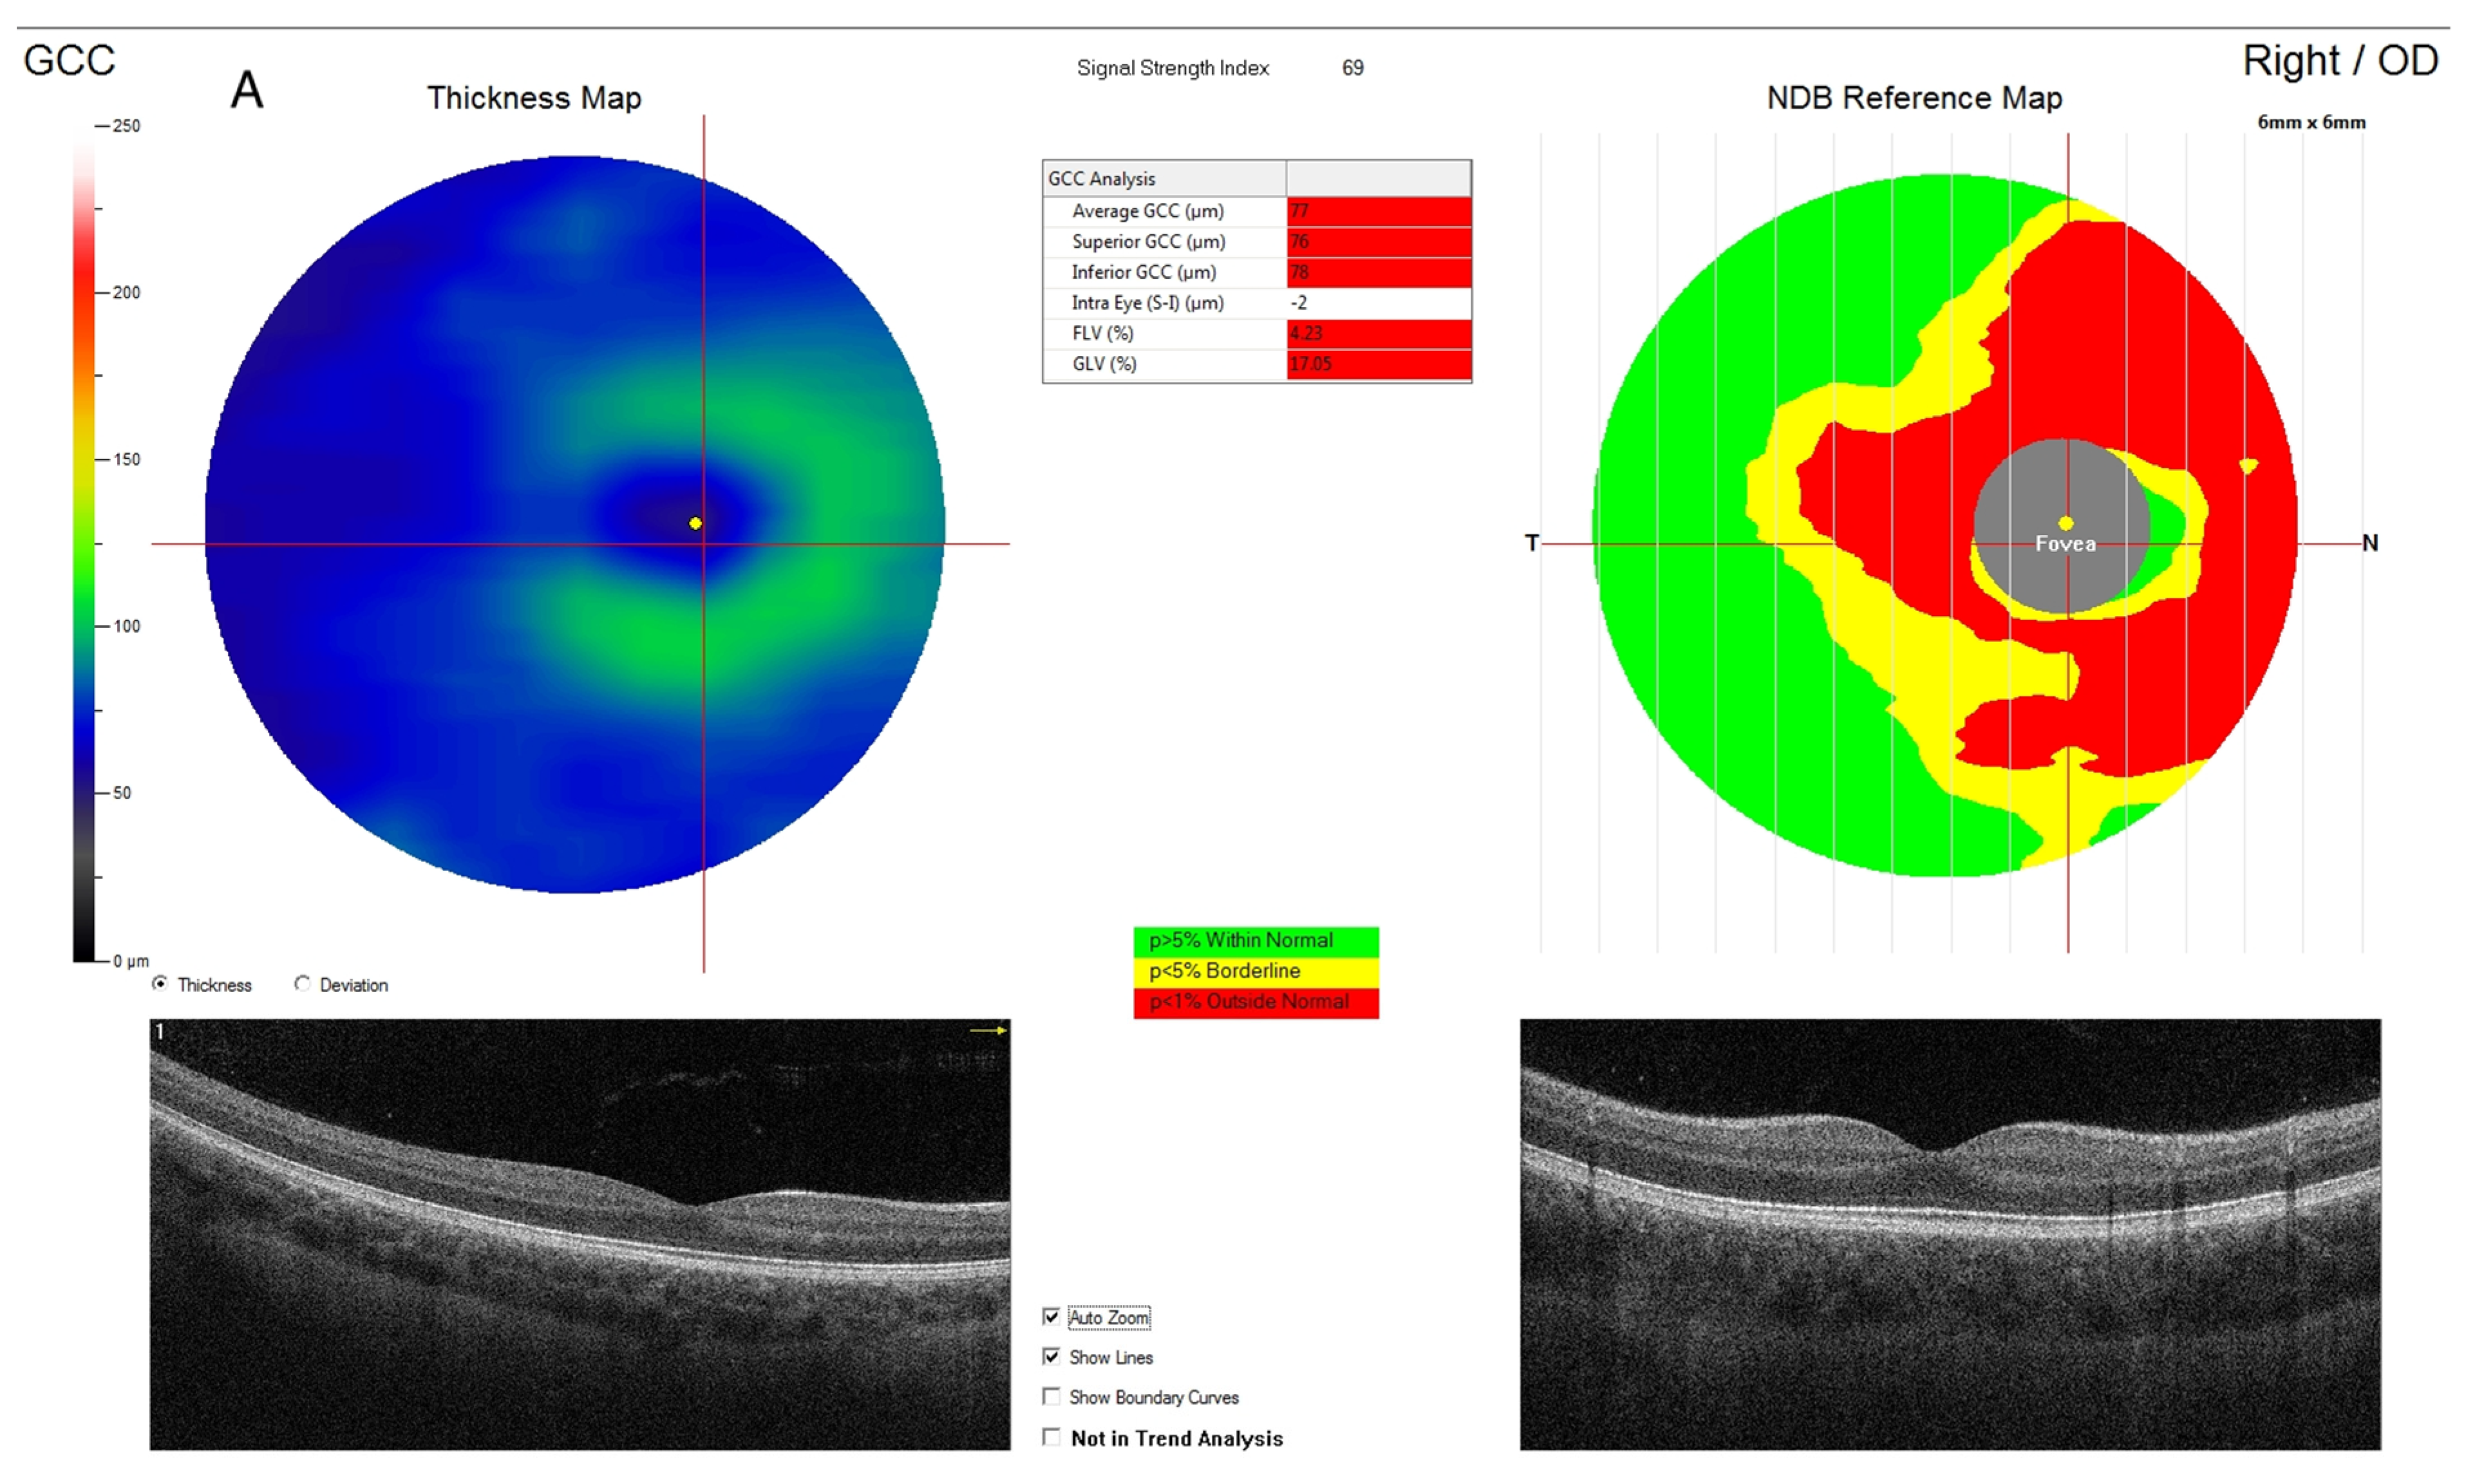

4.2. Ganglion Cell Complex

| Average GCC (μm) | 93 (86–100) | 203 | 100 (96–103) | 165 | <0.001 |

| GCC superior quandrant | 92 (85–98) | 203 | 99 (94–104) | 165 | <0.001 |

| GCC inferior quadrant | 93 (87–101) | 203 | 100 (96–104) | 165 | <0.001 |